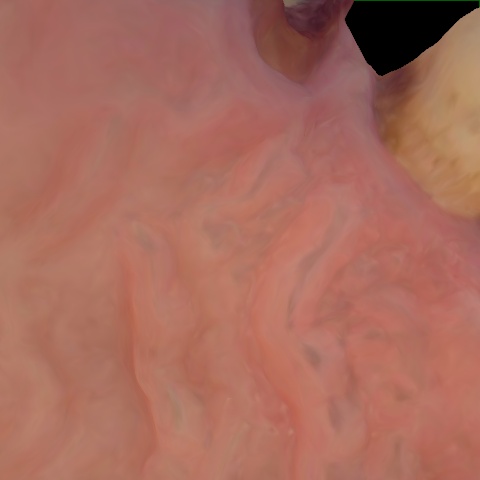

Annotated as "Good"